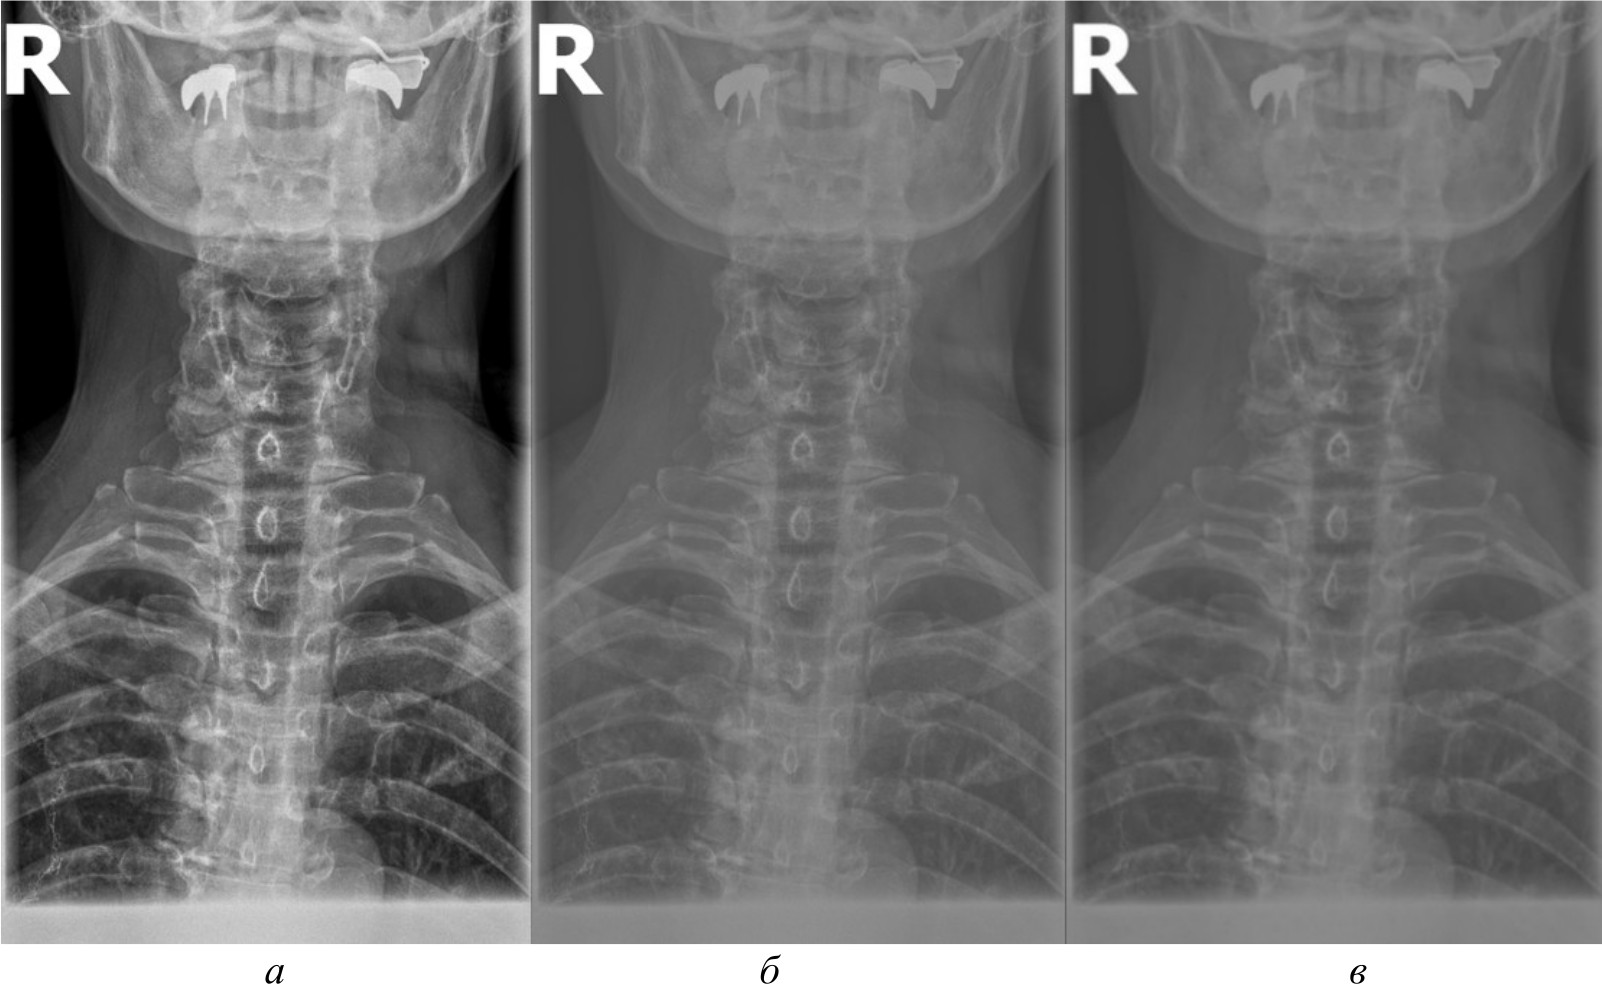

Автоматизированное распознавание таких ключевых анатомических ориентиров на рентгеновских изображениях представляет собой важную задачу, решение которой может повысить точность и скорость медицинской диагностики, обеспечив врачей объективной информацией для принятия решений. Компьютерное зрение способно автоматически локализовывать и идентифицировать анатомические структуры, измерять их размеры и взаимное расположение, а также выявлять отклонения от нормы, указывающие на наличие патологий. Однако недостаточное качество рентгеновских снимков, наличие помех, артефактов и неравномерностей может затруднять их восприятие системами компьютерного зрения. На рис. 1, а продемонстрирован рентгеновский снимок без предварительной обработки.

Рис. 1. Рентгеновский снимок без предварительной обработки (а); результаты работы детектора Harris на изображении без предварительной обработки (б)

Как видно на рис. 1, б, применение алгоритмов компьютерного зрения на необработанном изображении приводит к нечетким и неустойчивым результатам обнаружения ключевых анатомических ориентиров. Тем самым важной задачей, обеспечивающей эффективное применение алгоритмов компьютерного зрения, является разработка эффективных алгоритмов предварительной обработки изображений. Данные предварительной обработки, такие как улучшение контраста и устранение артефактов, служат основой для более точного и надежного анализа с использованием алгоритмов компьютерного зрения. Это позволяет повысить качество обнаружения ключевых анатомических ориентиров, играющих критическую роль в идентификации и оценке патологических изменений.